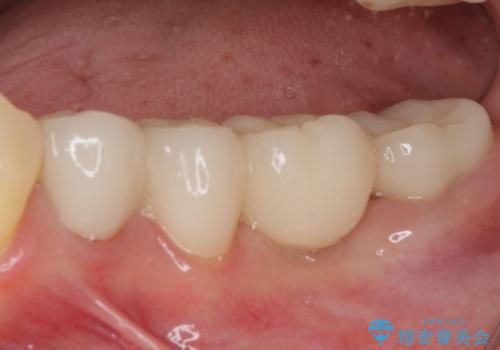

- 矯正治療中に装着していた仮歯を綺麗にしたいとのことで来院された患者様です。

小学生の頃に歯をぶつけて抜歯となりブリッジを装着したそうですが、その後矯正治療を行うに当たりブリッジを切断したとのことでした。

残っている歯根の状態はあまり良くなく、長期的な予後を考えると抜歯を検討するべきでしたが、20代前半という年齢を考え、オールセラミックブリッジにて補綴治療を行うこととしました。

歯肉ラインを整えるために歯肉移植術を行うか悩んでいましたが、行わないという判断をされたため、やや不揃いの歯肉ラインとなりました。